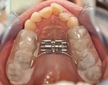

Çeneyi Nasıl İleri Alabilirim?Çene yapısı, yüz estetiği ve fonksiyonu açısından önemli bir rol oynamaktadır. Çenenin ileri ya da geri pozisyonu, yüz simetrisi, diş sağlığı ve genel estetik algı üzerinde belirleyici etkilere sahiptir. Bu makalede, çenenin nasıl ileri alınabileceği üzerine çeşitli yöntemler ve teknikler ele alınacaktır. 1. Ortodontik Tedavi YöntemleriOrtodontik tedavi, dişlerin ve çenenin düzgün bir şekilde hizalanmasını sağlamak amacıyla kullanılan bir yöntemdir. Çenenin ileri alınmasında aşağıdaki ortodontik yaklaşımlar etkili olabilir: